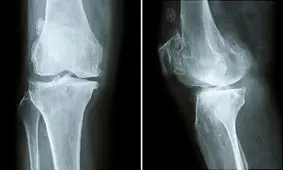

دکتر مریم امینی درباره پوکی استخوان گفت: سلولهای استخوانی بدن در شکل طبیعی خود شبیه لانههای زنبور است، اما در این…